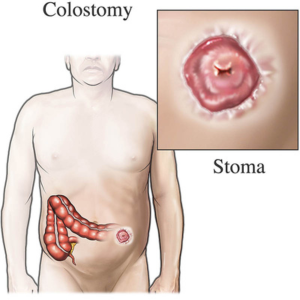

Emergency Colostomy

Stoma Care